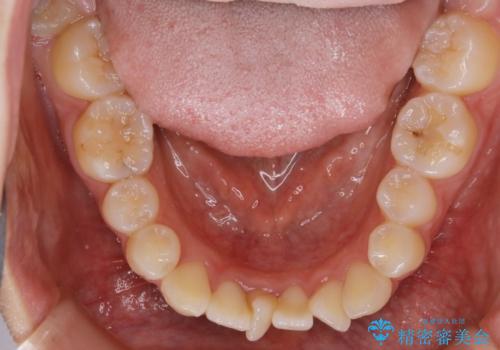

- 上下の歯のガタつきを主訴にご来院されました。

前歯部に特にガタつきが見られ、正中もズレている状態でした。

矯正装置の希望がインビザラインだったため、マイクロインプラントを併用し、奥歯から順に遠心移動をかけていくことにより非抜歯でも主訴のガタつきを治すことができました。